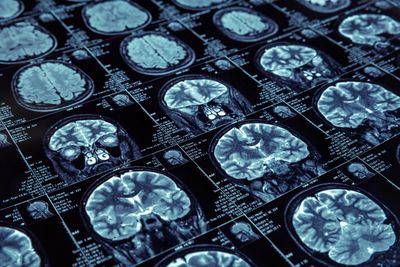

Clinical neuropsychologists have a special interest in cognition and the brain, investigating relationships between brain function and behaviour.

Clinical neuropsychologists conduct comprehensive cognitive assessments, which measure a person’s cognitive strengths and weaknesses.

Neuropsychological assessments measure cognitive abilities such as memory, attention, language, and executive functioning , and determine how these may impact a patient’s daily functioning.